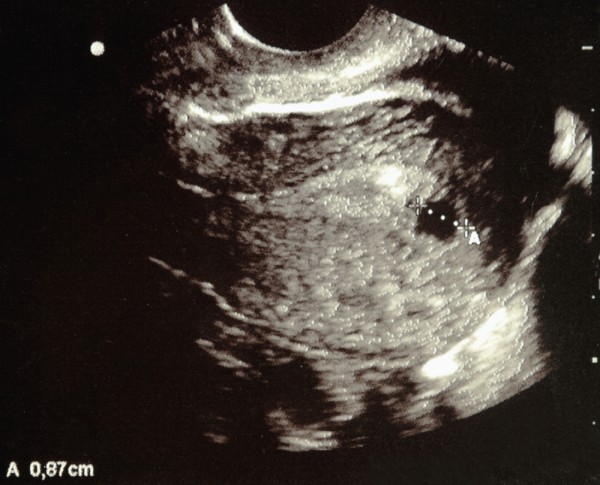

Узи

Ультразвуковое исследование позволяет определить наличие беременности на 6-й неделе, обнаруживая плодное яйцо в маточной полости. Его размер достигает 25 мм, а сам эмбрион составляет около 2-5 мм. Во время сканирования врач фиксирует увеличение матки и прикрепление эмбриона к одной из стенок (задней, передней или боковой). На экране будущий ребенок выглядит как маленькая черная точка или запятая.

Ключевым признаком беременности является сердцебиение плода, которое уже можно зафиксировать с помощью датчика.

Что покажет УЗИ в 6 недель беременности?

На 6-й неделе уже получится определить многоплодную беременность. Размеры плодного яйца. Этот показатель необходим врачам для уточнения срока гестации. Сердцебиение эмбриона.